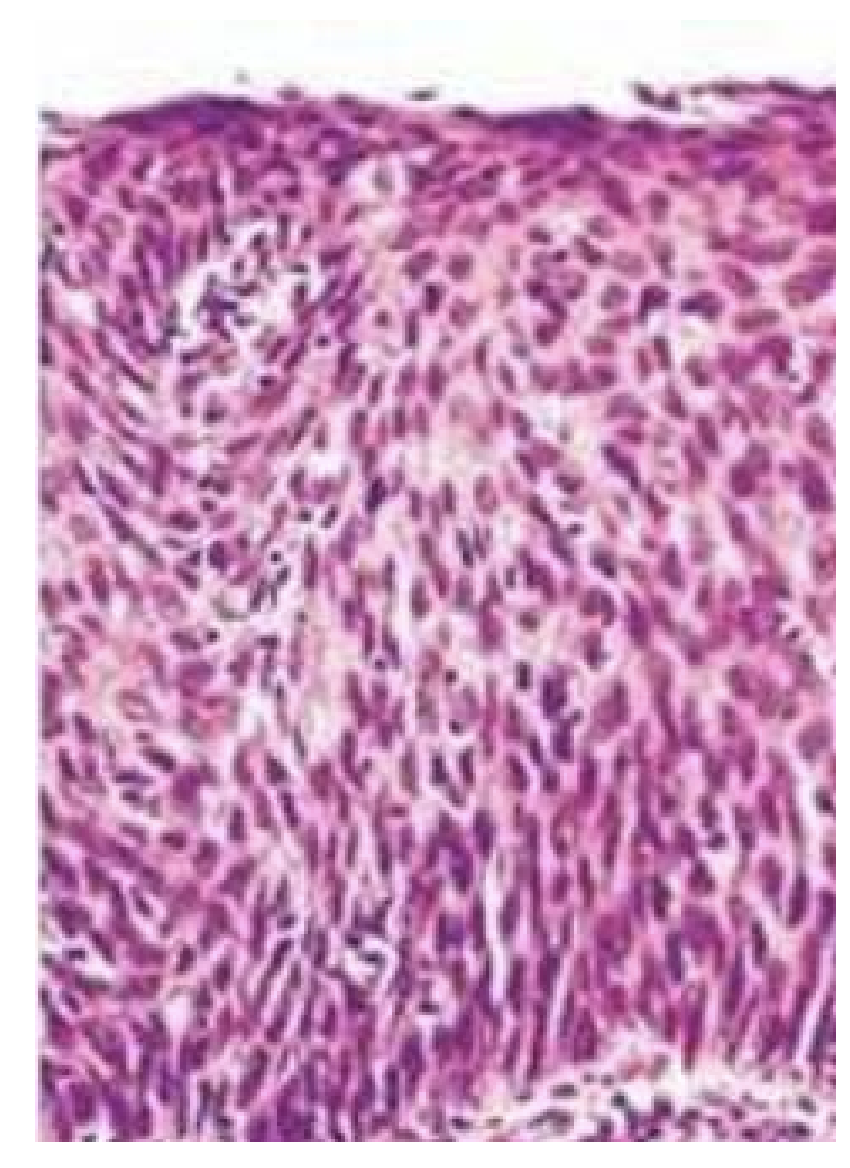

Hvilken histologisk diagnose passer bedst til billedet?

a. Adenom

b. Højt differentieret adenokarcinom

c. Leiomyom

d. Højt differentieret planocellulært karcinom

e. Lavt differentieret karcinom